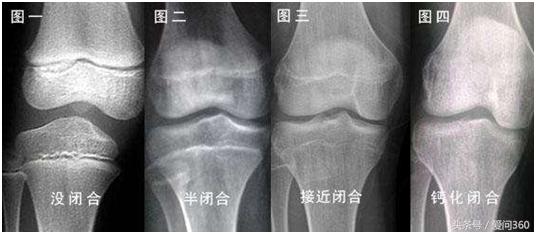

关于20岁能不能长高的问题,小编查阅了相关资料,其实对于一些骨骺闭合得比较晚的人体,20岁以后,经过合理的饮食和锻炼是可以长高的。那么如何知道自己是否骨骺已经完全闭合了呢?很简单,去医院拍个x光就知道了。其实很多人在20岁左右的时候,骨骺还是没有完全闭合的,可以通过后天合理的运动和饮食长个子的。下面小编给大家介绍几个长个子的运动操,不仅可以拉伸身高,还能使我们的身材更加匀称好看。